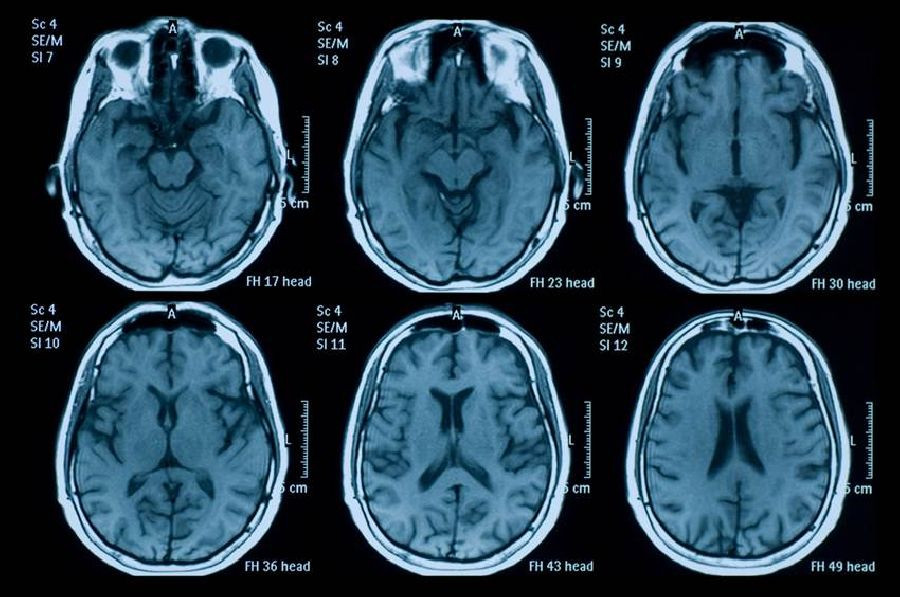

Un equipo de investigadores internacionales liderados por la compañía Aivocode, una `spin-off` del institudo Sanford Burnham Prebys de San Diego (Estados Unidos), ha identificado un "significativo" efecto neuroprotector del compuesto CAQK en modelos de ratón y cerdo de traumatismo craneoencefálico.

El estudio, publicado en la revista 'EMBO Molecular Medicine', ha mostrado como este péptido formado por cuatro aminoácidos se dirige específicamente a las zonas dañadas del cerebro tras ser inyectado por vía intravenosa poco después de la lesión, "atraído" por las glicoproteínas, que están presente en mayor cantidad en las zonas lesionadas tras un traumatismo.

CAQK se acumula en las zonas marcadas por la proteína y logra reducir tanto la inflamación como la muerte celular y el daño en el tejido cerebral, mejorando también la recuperación funcional, sin mostrar toxicidad aparente en ratones, lo que abre "nuevas posibilidades" a tratar zonas lesionadas del cerebro.